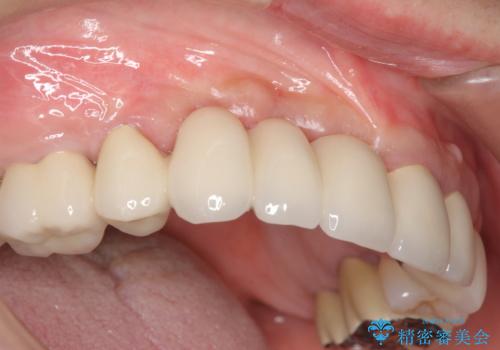

咬合性外傷による歯槽骨吸収 ブリッジ補綴

保存の難しい歯の抜歯、保存できる歯の歯周病治療、欠損部位の歯槽堤形態回復を含めブリッジによる安定した咬合機能回復を計画します。

- 90万円 (仮歯×9 メタルボンドクラウン×9)費用は治療当時の料金となります

ブリッジは欠損した部位に臨在する歯を削り、被せなければいけないというデメリットがありますが反面噛む力が強い場合連結することで強大な咬合力に対抗できるというメリットも存在します。